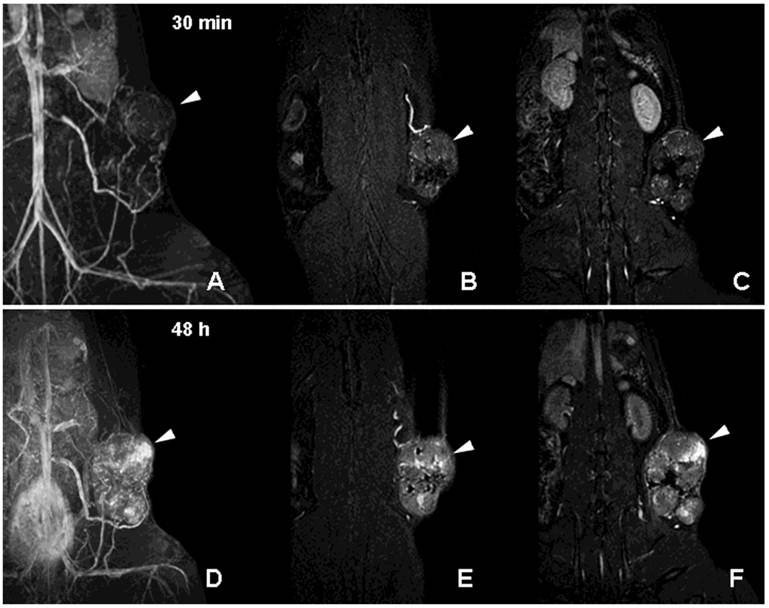

Figure 6

MR imaging of tumor neovascularity and interstitial leakage in a rat model of adenocarcinoma. A-C- a MIP projection (A) and two non-consecutive MR imaging slices obtained 30 min after I.V injection of PGC-DTPA(Gd) in rats with R3230 adenocarcinoma. D-F - MR images obtained in the same animal 48 h after the injection of PGC-DTPAGd. Note accumulation in the tumor at 48 h (the location of the tumor is shown by arrowheads). For MR imaging conditions see Figure 4A, legend. Adapted from [40].

Neovascularization is one of the key characteristics of tumor growth [39]. Although neovascularity of a solid tumor does not necessarily imply malignancy, extensive sprouting of capillaries in malignant tumors has been shown to correlate with metastatic potential [39]. Non-invasive detection of altered tumor vessels is potentially important in biopsy planning, staging and in treatment evaluation (since decreased vascularized margins can be indicative of tumor regression). We initially used PGC-DTPAGd-assisted MR imaging for detecting the increase of the diameter of host vessels, e.g. epigastric vein, as an early sign of tumor progression in a rat model of mammary adenocarcinoma [40]. Six to 8 days after tumor implantation, vessels at the tumor/host interface became clearly visible by MRI. At later stages of tumor development, we observed formation of tumor blood vessels with abnormal morphology (Fig. 6A-C). Time-delayed imaging of the same animals (48 h post IV administration) revealed the enhanced leakage of PGC from immature and permeable tumor blood vessels (Fig. 6D-F) Therefore, PGC-DTPAGd-generated vessel enhancement of MR signal is effective in tracking the developing vascular tumor architecture non-invasively in vivo. The method is sensitive in the whole volume of the tumor at even early time points and has the capacity to be instrumental in detecting areas of enhanced vascular permeability.